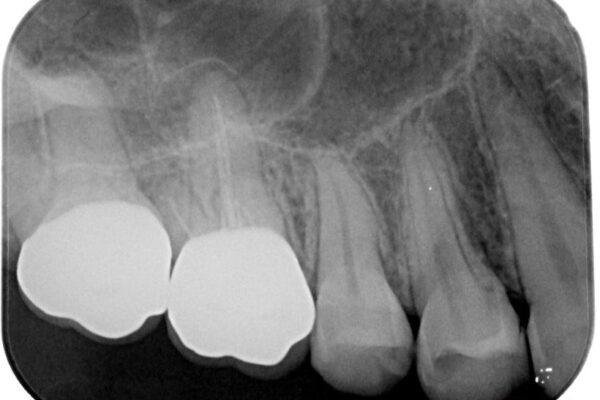

インプラント希望部位は右下第一大臼歯と第二大臼歯です。

しかし、噛み合わせの相手である右上の第二大臼歯が、長期間噛み合う歯がなかった影響で**挺出(歯が下に伸びてくる状態)してしまっており、このままではインプラントを埋入して被せもの(上部構造)を入れるためのスペースが不足している状態でした。

• 挺出歯を圧下してスペースを確保!目立たない部分矯正で下顎大臼歯にインプラント治療を実現 治療前画像